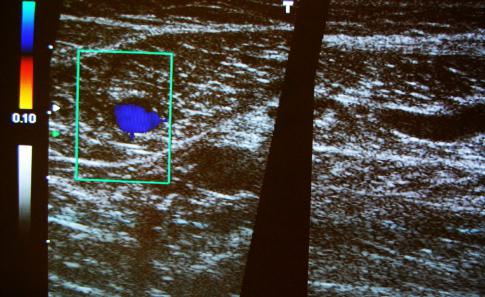

Farbduplexuntersuchungen

Die Farbduplexuntersuchungen vereinigt das klassische

Ultraschallbildes eines Gefäßes mit Informationen über die

Durchblutung. Diese wird farbig kodiert dargestellt und

ermöglicht es dem Untersucher Rückschlüse auf Engstellungen

Blutflußverlangsamungen ( wie z.B bei Thrombosen) zu stellen.

Farbduplexuntersuchungen können von uns an den Halsgefäßen,

den Beingefäßen sowie auch den Nierengefäßen durchgeführt werden.

Wir weisen darufhin, dass Farbduplexuntersuchung in unserer Praxis

auf Grund der Nierderlassung als Hausärztlich tätige Internisten

nur Privat angeboten weden können.